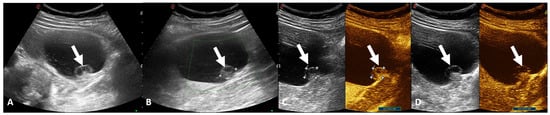

2. Ultrasound Assessment

3. Contrast-Enhanced Ultrasound Assessment